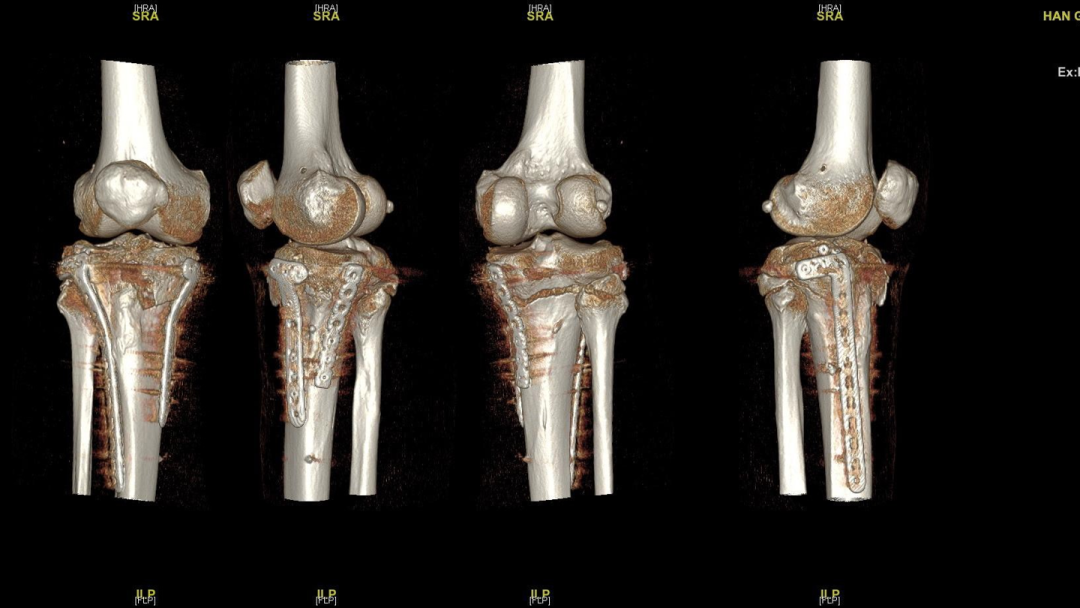

过伸型胫骨平台骨折的治疗,超详细解析!